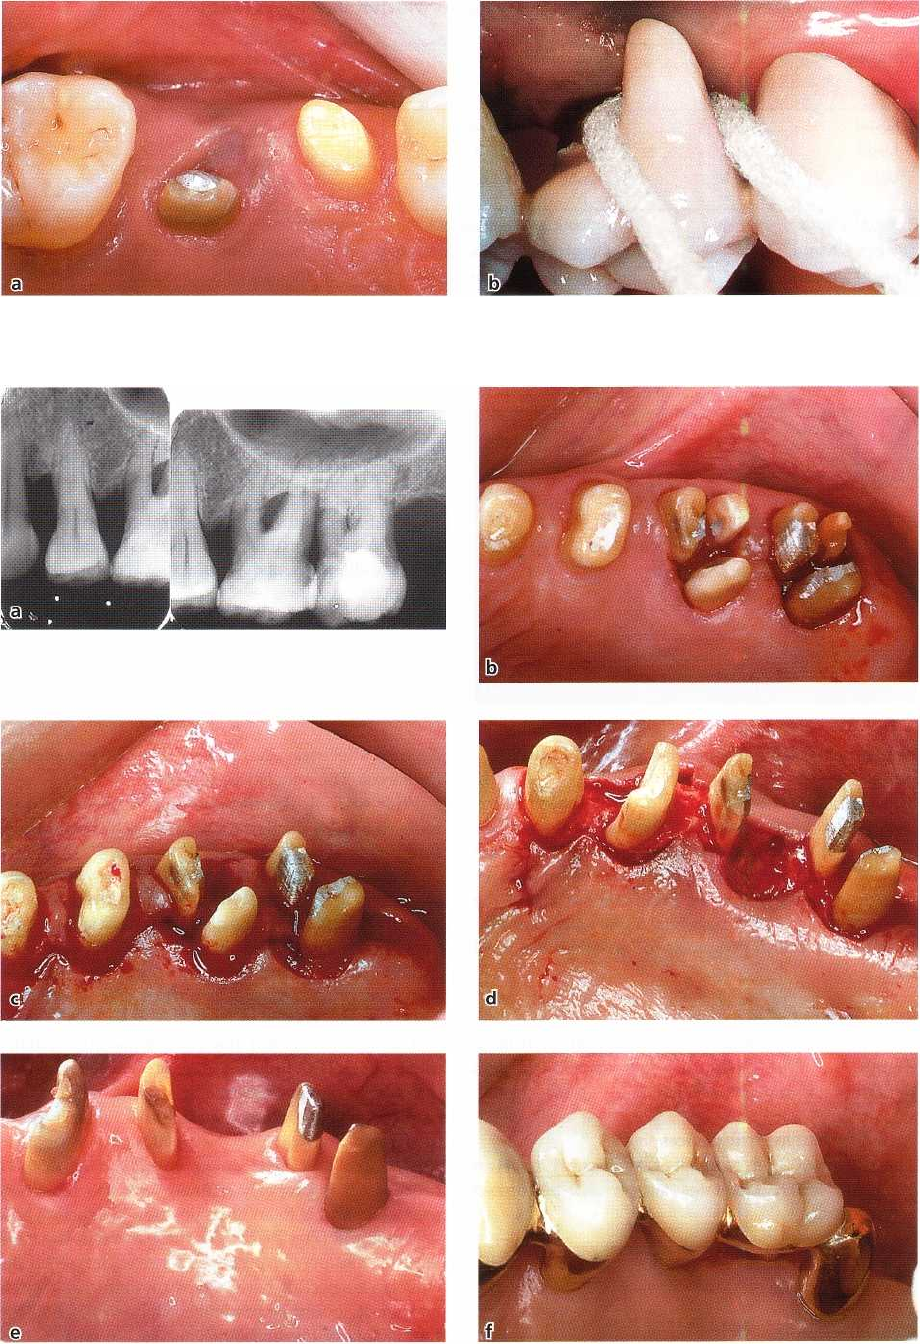

Fig. 29-28. Resection of the dis

tobuccal root of a three-rooted

maxillary first premolar.

The series of illustrations presented in Fig. 29-27

demonstrates two left maxillary molars (teeth 26 and

27) with degree III involvement of all six furcation

entrances. Both teeth were, following a detailed ex-

amination and diagnosis, scheduled for treatment

with RSR. Note that in this case the second premolar

was missing. In cases of advanced periodontal disease

at maxillary molars, it is often necessary to separate

all three roots of the individual tooth to obtain access

to the interradicular area for assessment of the height

of the remaining bone at (1) the buccal surface of the

palatal root and (2) the palatal surfaces of the buccal

roots. Fig. 29-27b illustrates the two maxillary molars

with all six roots separated. Because of anatomic con

siderations and increased mobility, the distobuccal

roots of 26 and 27 were extracted (Fig. 29-27c). The

palatal root of the first molar had a deep area of

localized attachment loss on its buccal surface, was

considered to be a poor candidate for a bridge abut-

ment and was extracted. The mesiobuccal root of the

first molar as well as the mesiobuccal and palatal roots

of the second molar (27) were stable and exhibited

moderate probing depth. It was anticipated that at all

three roots the anatomy following healing after treat-

ment would allow proper plaque control. The three

roots were maintained (Fig. 29-27d). Fig. 29-27e shows

the area after 3 months' healing and Fig. 29-27f illus-

trates the segment properly restored. Since in this

segment one premolar was missing, the mesiobuccal

root of the first molar was used as second premolar in

the prosthetic reconstruction and the two roots of the

second molar served as abutments for a crown resto-

ration in the position of a molar.

Root resection of maxillary first premolars is possible

only in rare instances due to the anatomy of the root

complex (Joseph et al. 1996) (Fig. 29-28a,b). The furca

tion of this premolar is often located at such an apical

level that the maintenance of one root serves no mean

-

ingful purpose. In most cases, therefore, the presence

of a deep furcation involvement of degree II or degree

III in a maxillary first premolar calls for tooth extrac-

tion.